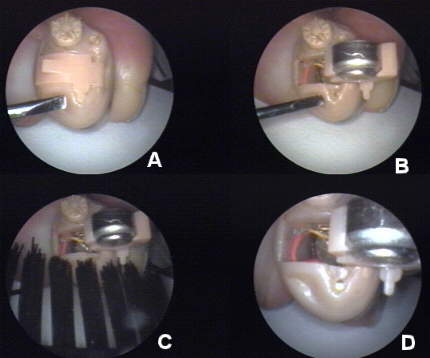

Figure A (inline image, below; A-D=16k) shows the basis for a "dead" minicanal hearing aid. Because the microphone is located in such intimate proximity to the VC, sebum and desquamation are constantly being "shaved off" into the edges of the microphone protective cover, providing a "gasket grease" seal when the battery compartment (BC) / microphone cover is closed.

Figure B shows the sebum/desquamation accumulation within the microphone antechamber.

The process of using the wax (mascara) brush to clean organic debris from the exposed microphone antechamber is demonstrated for the patient (Figure C).

Figure D presents the results of the microphone cleaning process.